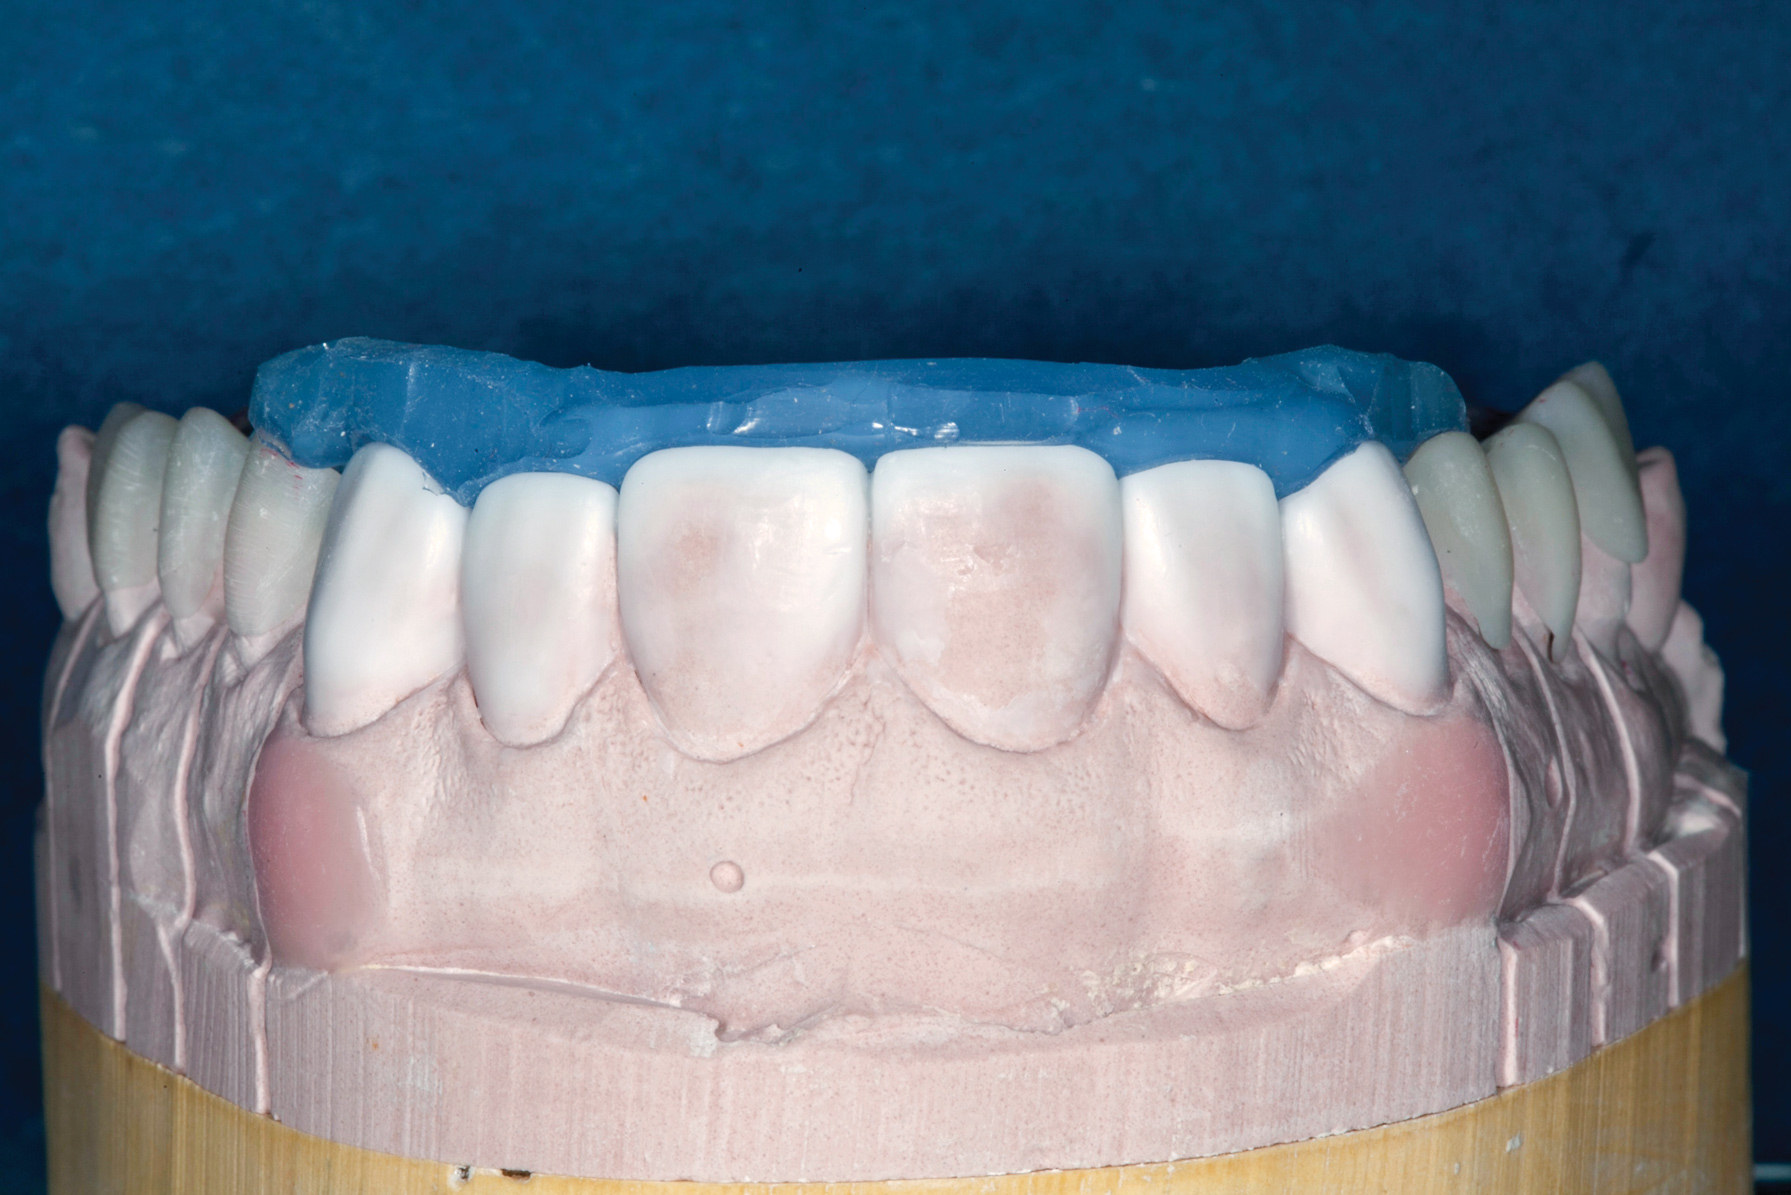

(7.) Lingual matrix in place.

Figure 7

During subsequent appointments, teeth Nos. 4 through 13 were restored with direct composite veneers in stages. Teeth Nos. 6 through 12 were treated first, followed by teeth Nos. 4, 5, and 13, respectively. Lingual and facial silicone putty indices were fabricated from the wax-up (Figure 7), and the lingual matrix was marked with a sharp probe at the existing incisal edge. Next, low-pressure air abrasion was used to clean the area and roughen the enamel to be bonded. Teeth Nos. 4 and 12 were isolated using polytetrafluoroethylene plumber's tape, and a 37.5 % phosphoric acid etching gel was applied and rinsed off. A layer of a fifth-generation bonding agent was applied and air-thinned, then a second layer was applied, air-thinned, and cured. The application of two layers has been shown to produce an increase in microtensile bond strength.20 After placement of the bonding agent, a clear enamel shade of microhybrid composite was applied into the lingual matrix in a thin layer and drawn slightly over the previously marked line. The composite was thickened toward the facioincisal line angle, which creates a natural "halo effect." The matrix was then adapted to the teeth, and the lingual shelf was briefly cured (Figure 8).